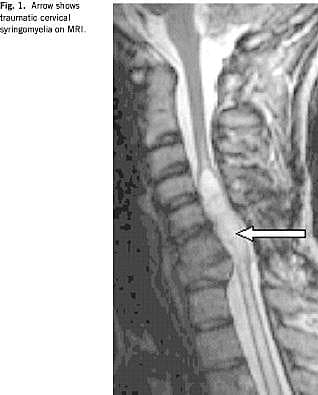

Der er opnået en vis enighed om at definere PTS som en cystisk udvidelse i rygmarven, der strækker sig over mindst to ryghvirvellegemers højde og som bedømt ved MR har samme signalintensitet som væske, dvs. lav på T1-vægtede og høj på T2-vægtede billeder [5-7] (Fig. 1 ). Den cystiske udvidelse er oftest lokaliseret decentralt ud for frakturstedet, men kan kommunikere med centralkanalen proksimalt eller distalt herfor.